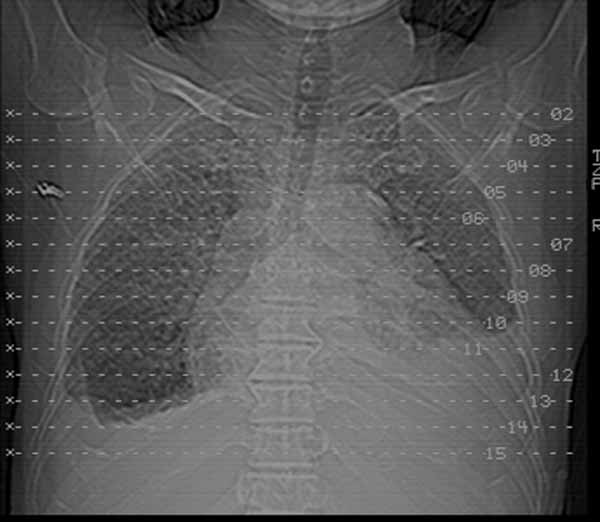

以下是引用余辉在2009-3-31 18:43:00的发言:[br]肺水肿,双侧心腔积液,心包积液,心影增大,疑似心衰

以下是引用wangyong1977在2009-3-31 20:46:00的发言:[br]肺水肿,双侧胸腔积液,心包积液,心影增大,疑似心衰 [br]

以下是引用宇宙ct在2009-3-31 18:57:00的发言:[br]肺水肿,双侧心腔积液,心包积液,心影增大,疑似心衰 [br] [br]